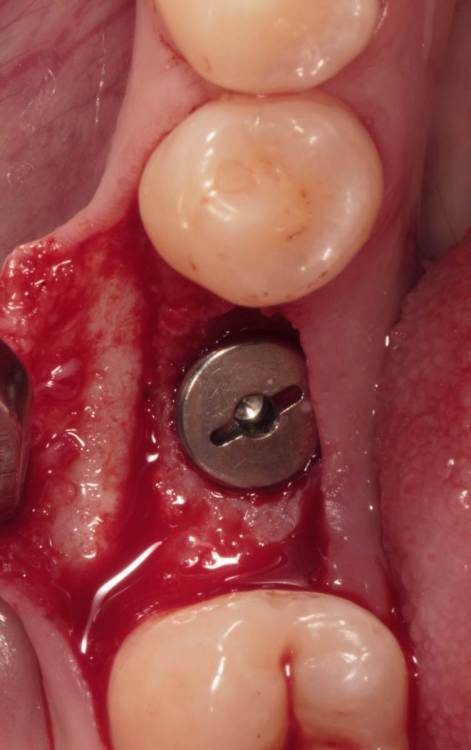

Женька Опубликовано 19 августа, 2023 Поделиться Опубликовано 19 августа, 2023 ?️. Поймал себя на мысли, что испытываю проблемы с ушиванием+ССТ на формике. А именно-не устраивает результат "прирощённой" десны. Вроде на ушивании есть + к объёму, а на протезировании "яма" вестибулярно лишь немного уменьшилась. Подскажите, как лоскут формировать так, чтобы в слоёном пироге имплантат-формик-сст оставался объём слизистой, а не таял. Подумал, что может стоит при имплантации сразу формировать асл. А в кейсе я снова "согрешил" и поставил ультра-низкий формик. В этот раз без всяких послаблений лоскута и натяжения, кмк. Ссылка на комментарий

Женька Опубликовано 19 ноября, 2023 Автор Поделиться Опубликовано 19 ноября, 2023 (изменено) прошло 3 месяца. Изменено 19 ноября, 2023 пользователем Женька порядок фоток 1 Ссылка на комментарий

annda Опубликовано 23 ноября, 2023 Поделиться Опубликовано 23 ноября, 2023 Не жалуются на боли? Формик ниже края слизистой такое себе Ссылка на комментарий

Женька Опубликовано 23 ноября, 2023 Автор Поделиться Опубликовано 23 ноября, 2023 @annda неа, пока ни одной жалобы не услышал Ссылка на комментарий